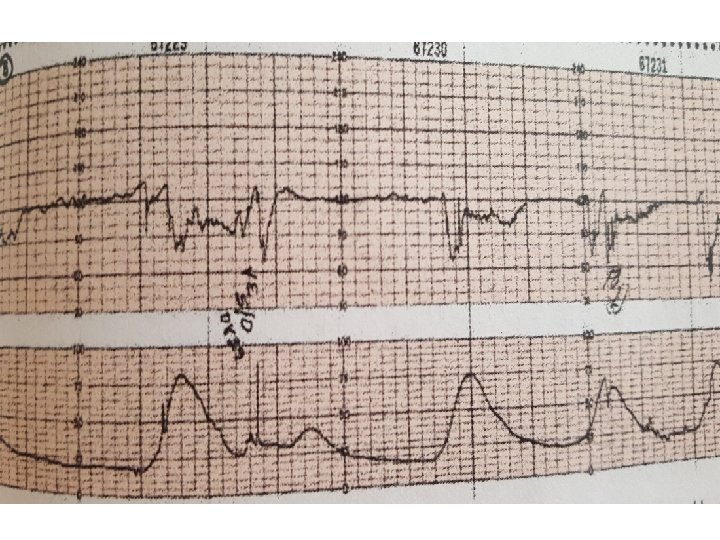

Variable Deceleration Typical: • shoulders Atypical : • Overshoot • Loss of primary shoulder • Slow return to baseline (late component) • Baseline returns to a lower level(after deceleration) • Biphasic(W shape) • loss of variability during deceleration

Complicated variable deceleration Indicated fetal hypoxia • Tachycardia • Lack of variability • Slow return to baseline • Large amplitude(to 60 bpm or duration 60 second) • Loss of pre and post shouldering • Smooth overshoot

variable decelerations with absent to minimal variability

Variable decelerations with minimal to absent variability

Tachycardia and variable decels with late recovery